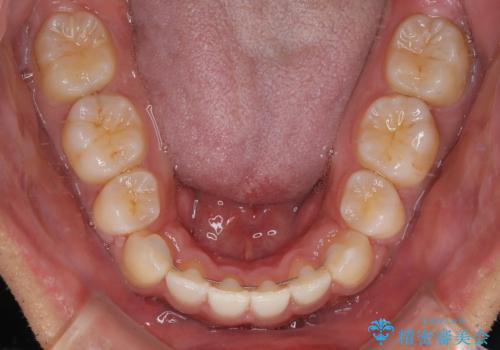

八重歯はきれいに整い、前歯もバランスよく収まり、横顔のラインも自然に改善されました。

治療後、患者様は「思い切り笑えるようになった」と大変喜んでくださいました。